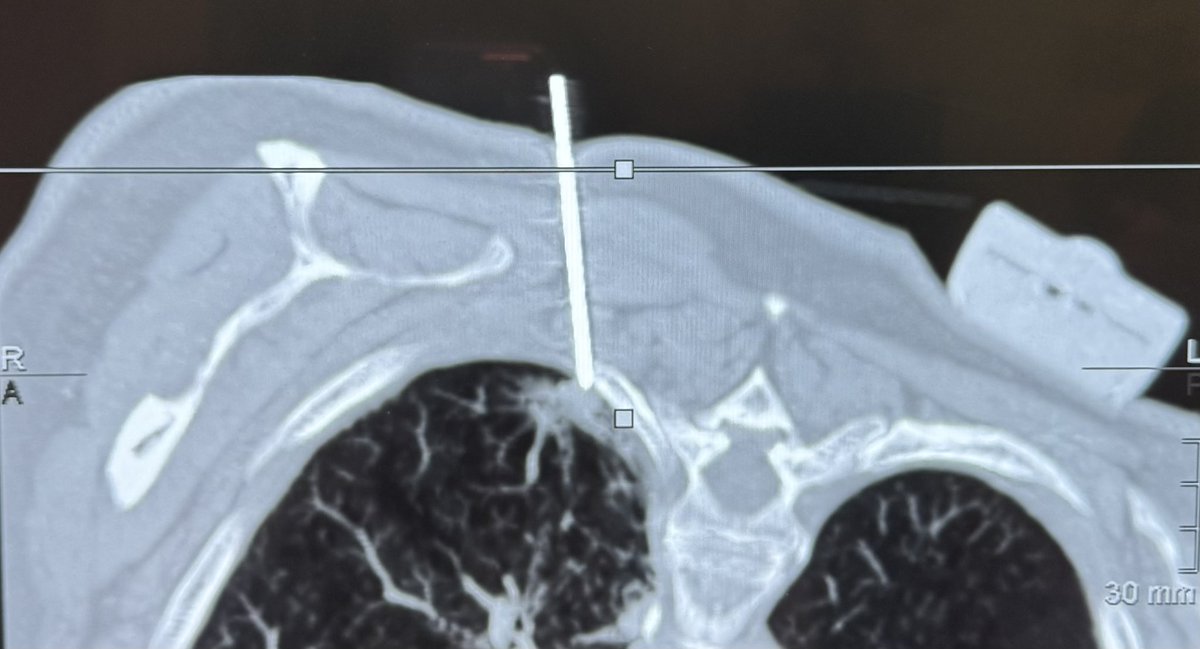

La sección de Intervencionismo de nuestro servicio ha realizado varias biopsias guiadas por un sistema de navegación en TC. Permite disminuir el número de punciones y la dosis de radiación administrada al paciente. CAHU Área Sanitaria V @GEHealthCare_ES IMACTIS CT-Navigation